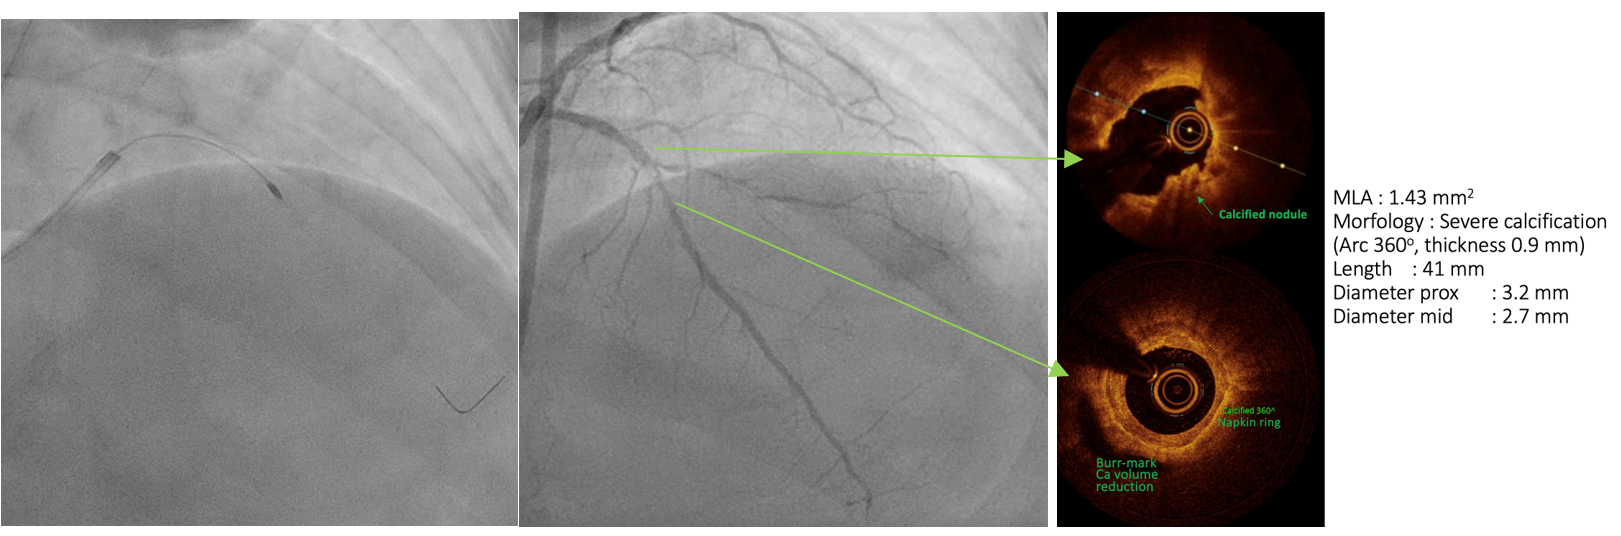

PCIof the LAD was performed via femoral access using a BL 3.5/7F guiding catheter.A Runthrough Hypercoat wire was advanced distally without difficulty. The OCTcatheter failed to cross the lesion, and a 2.5 ¡¿ 15 mm scoring balloon couldnot pass the mid LAD. A microcatheter was inserted, and the wire was exchangedfor a Rotawire. Rotational atherectomy was performed using a 1.25 mm burr withshort, gentle pecking runs at 180,000 rpm, followed by upsizing to a 1.5 mmburr for three runs at 200,000 (2 times) and 160,000 rpm. The burr advancedsmoothly with improved tactile feedback, suggesting successful plaquemodification. The wire was exchanged back to a Runthrough, and OCT (DragonflyOPTIS) imaging showed an MLA of 1.43 mm©÷ at mid LAD with severe 360¡Æ calcification(0.9 mm thick, 41 mm long) and a napkin-ring pattern. A 2.5 ¡¿ 15 mm cuttingballoon was used with multiple 14–18 atm inflations, producing a visible¡°crack¡± in the calcified cap. Angiography and repeat OCT confirmed the calciumfracture. A 3.0 ¡¿ 46 mm DES was deployed from the ostial to distal LAD at 14atm and post-dilated with a 3.5 mm NC balloon proximally. Final angiographyshowed TIMI 3 flow. OCT demonstrated excellent stent expansion (MSA 7.78 mm©÷proximal, 3.28 mm©÷ distal) without dissection and with 107% stent expansion.

This case shows the Rota-Cut strategy transforms a high-risk, unpredictable intervention into a controlled and successful one on a severely calcified "napkin ring" coronary lesion that is resistant to standard balloon dilation. Rotational atherectomy will reduced the volume of calcific plaque and cutting balloon will cause calcium fracture to facilitate optimal stent expansion and apposition confirmed on intravascular imaging and prevent stent failure in the future.